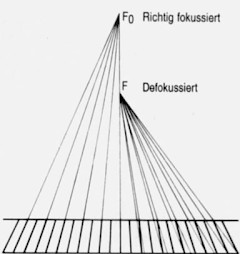

Ein fokussiertes Raster, ist ein Raster, bei dem sich die Ebenen der Rasterlamellen in einer Geraden im Fokussierungsabstand fo von der Rasterebene schneiden. Fokussierte Raster stellen hohe Ansprüche an Zentrierung und Fokussierung. Sie bieten dafür ein Optimum an Streustrahlenabsorption bei gleichzeitig maximaler Primärstrahlendurchlässigkeit.

Der fokussierte Raster ist ein plan ausgebildeter Raster, bei welchem die Rasterlamellen entsprechend dem gewünschten Fokussierungsabstand ausgerichtet sind. Am meisten benutzt werden die fokussierten Raster.

Der Fokussierungsabstand: fo ist der Abstand der Schnittgeraden der Lamellenebenen von der Rasterebene, z. B. fo = 115 d.h. der Raster – Fokus – Abstand beträgt 115 cm Bei Parallelrastern fo = ∞ (unendlich)

Defokussierung:

Anmerkung: Als defokussiert bezeichnet man die Lage eines Rasters, wenn der Abstand f zwischen dem Fokus und der Rasterebene nicht gleich dem Fokussierungsabstand fo ist ( f ≠ fo )

Richtig fokussiert(links) werden die Lamellen richtig nur als schmale Streifen abgebildet, während rechts die Lamellen zu immer breiteren Schatten werden von der Rastermitte nach außen gesehen.

Da bei einem Laufraster die Lamellen aber nicht zur Abbildung kommen, wirkt sich diese Verschattung bei Defokussierung zu einer Unterbelichtung der Aufnahme zum Rand hin aus.

Dasselbe vollzieht sich im Prinzip auch bei einer Vergrößerung des Fokus – Raster – Abstandes, allerdings kommt es hier aufgrund des geänderten Einfallwinkels der Strahlung nicht im selben Maß zur Abschattung. Selbstverständlich ist die Verschattung auch vom Schachtverhältnis des Rasters abhängig. Je höher das Schachtverhältnis desto mehr tritt dieser Effekt auf.